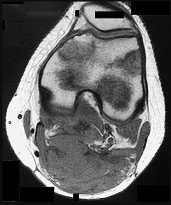

This patient has a dedifferentiated liposarcoma within a preexisting atypical lipomatous tumor. The imaging demonstrates a large fatty mass with increased internal septations proximally (the atypical lipomatous tumor) and a solid enhancing mass distally (the dedifferentiated portion). A biopsy reveals a high-grade liposarcoma. The other diagnostic responses do not reflect sarcomatous transformation of the lesion.

Surgical treatment of a high-grade sarcoma involves wide surgical resection. Radiation decreases local recurrence but does not clearly influence overall survival. The role of chemotherapy in high-grade soft-tissue sarcomas remains investigational; there is a modest (8%-15%) associated improvement in overall survival.

Intramuscular lipomas and atypical lipomatous tumors are treated with marginal resection alone. Radiation therapy for soft-tissue sarcomas may be given before or after surgery. When administered before surgery, patients have a higher wound complication rate but better long-term function attributable to lower rates of lymphedema, fibrosis, and contractures.